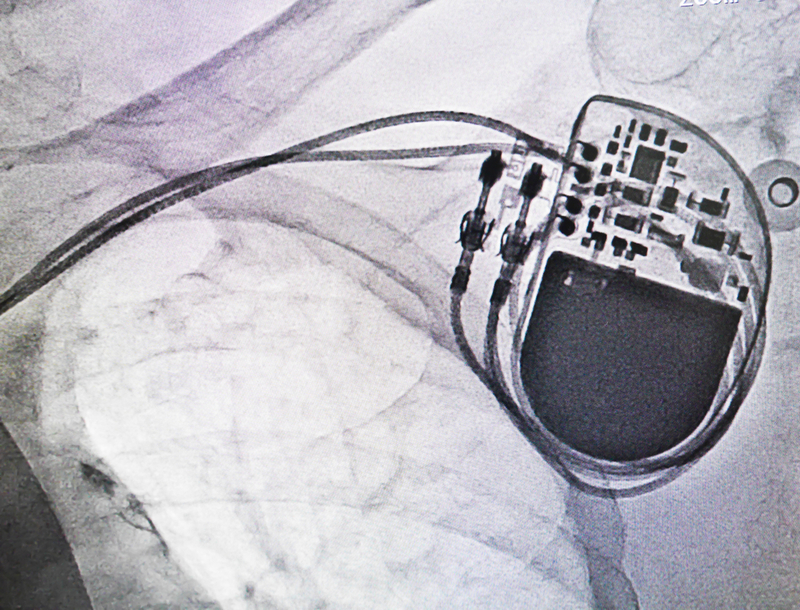

India's apex drug regulator Central Drugs Standard Control Organisation (CDSCO) has issued an alert about battery depletion issues in some pacemakers sold by the US-based medical device manufacturer Medtronic.

The world's largest medical device maker earlier published a performance note about a "rare mode" in a population of Azure and Astra pacemakers and Percepta, Serena and Solara cardiac resynchronisation therapy pacemakers (CRT-P).

In India, Astra pacemaker, Solara CRT-P and Serena CRT-P are available. "In consultation with our Independent Physician Quality Panel, we do not recommend device replacement, and advise physicians to continue normal patient follow-up in accordance with standard practice and, where possible, to continue with remote monitoring," Medtronic india said.